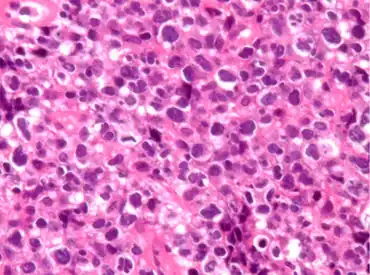

Pathological features observed during staining.

PMLBCL arises from a putative thymic peripheral B cell.[3][4] It has several distinctive biological features.[3] Molecular analysis shows that PMLBCL is distinct from other types of diffuse large B-cell lymphomas (DLBCL).[4] MAL gene expression is seen in 70%, unlike other diffuse large B-cell lymphomas.[2]:370 Gene expression profiling shows considerable variance from other DLBCLs and similarity to Hodgkin disease.[5]:290–293

PMLBCL is CD20 positive, expresses pan-B markers including CD79a, and has clonal immunoglobulin gene rearrangements and mRNA but paradoxically does not express cytoplasmic or cell surface immunoglobulin.[2]:370